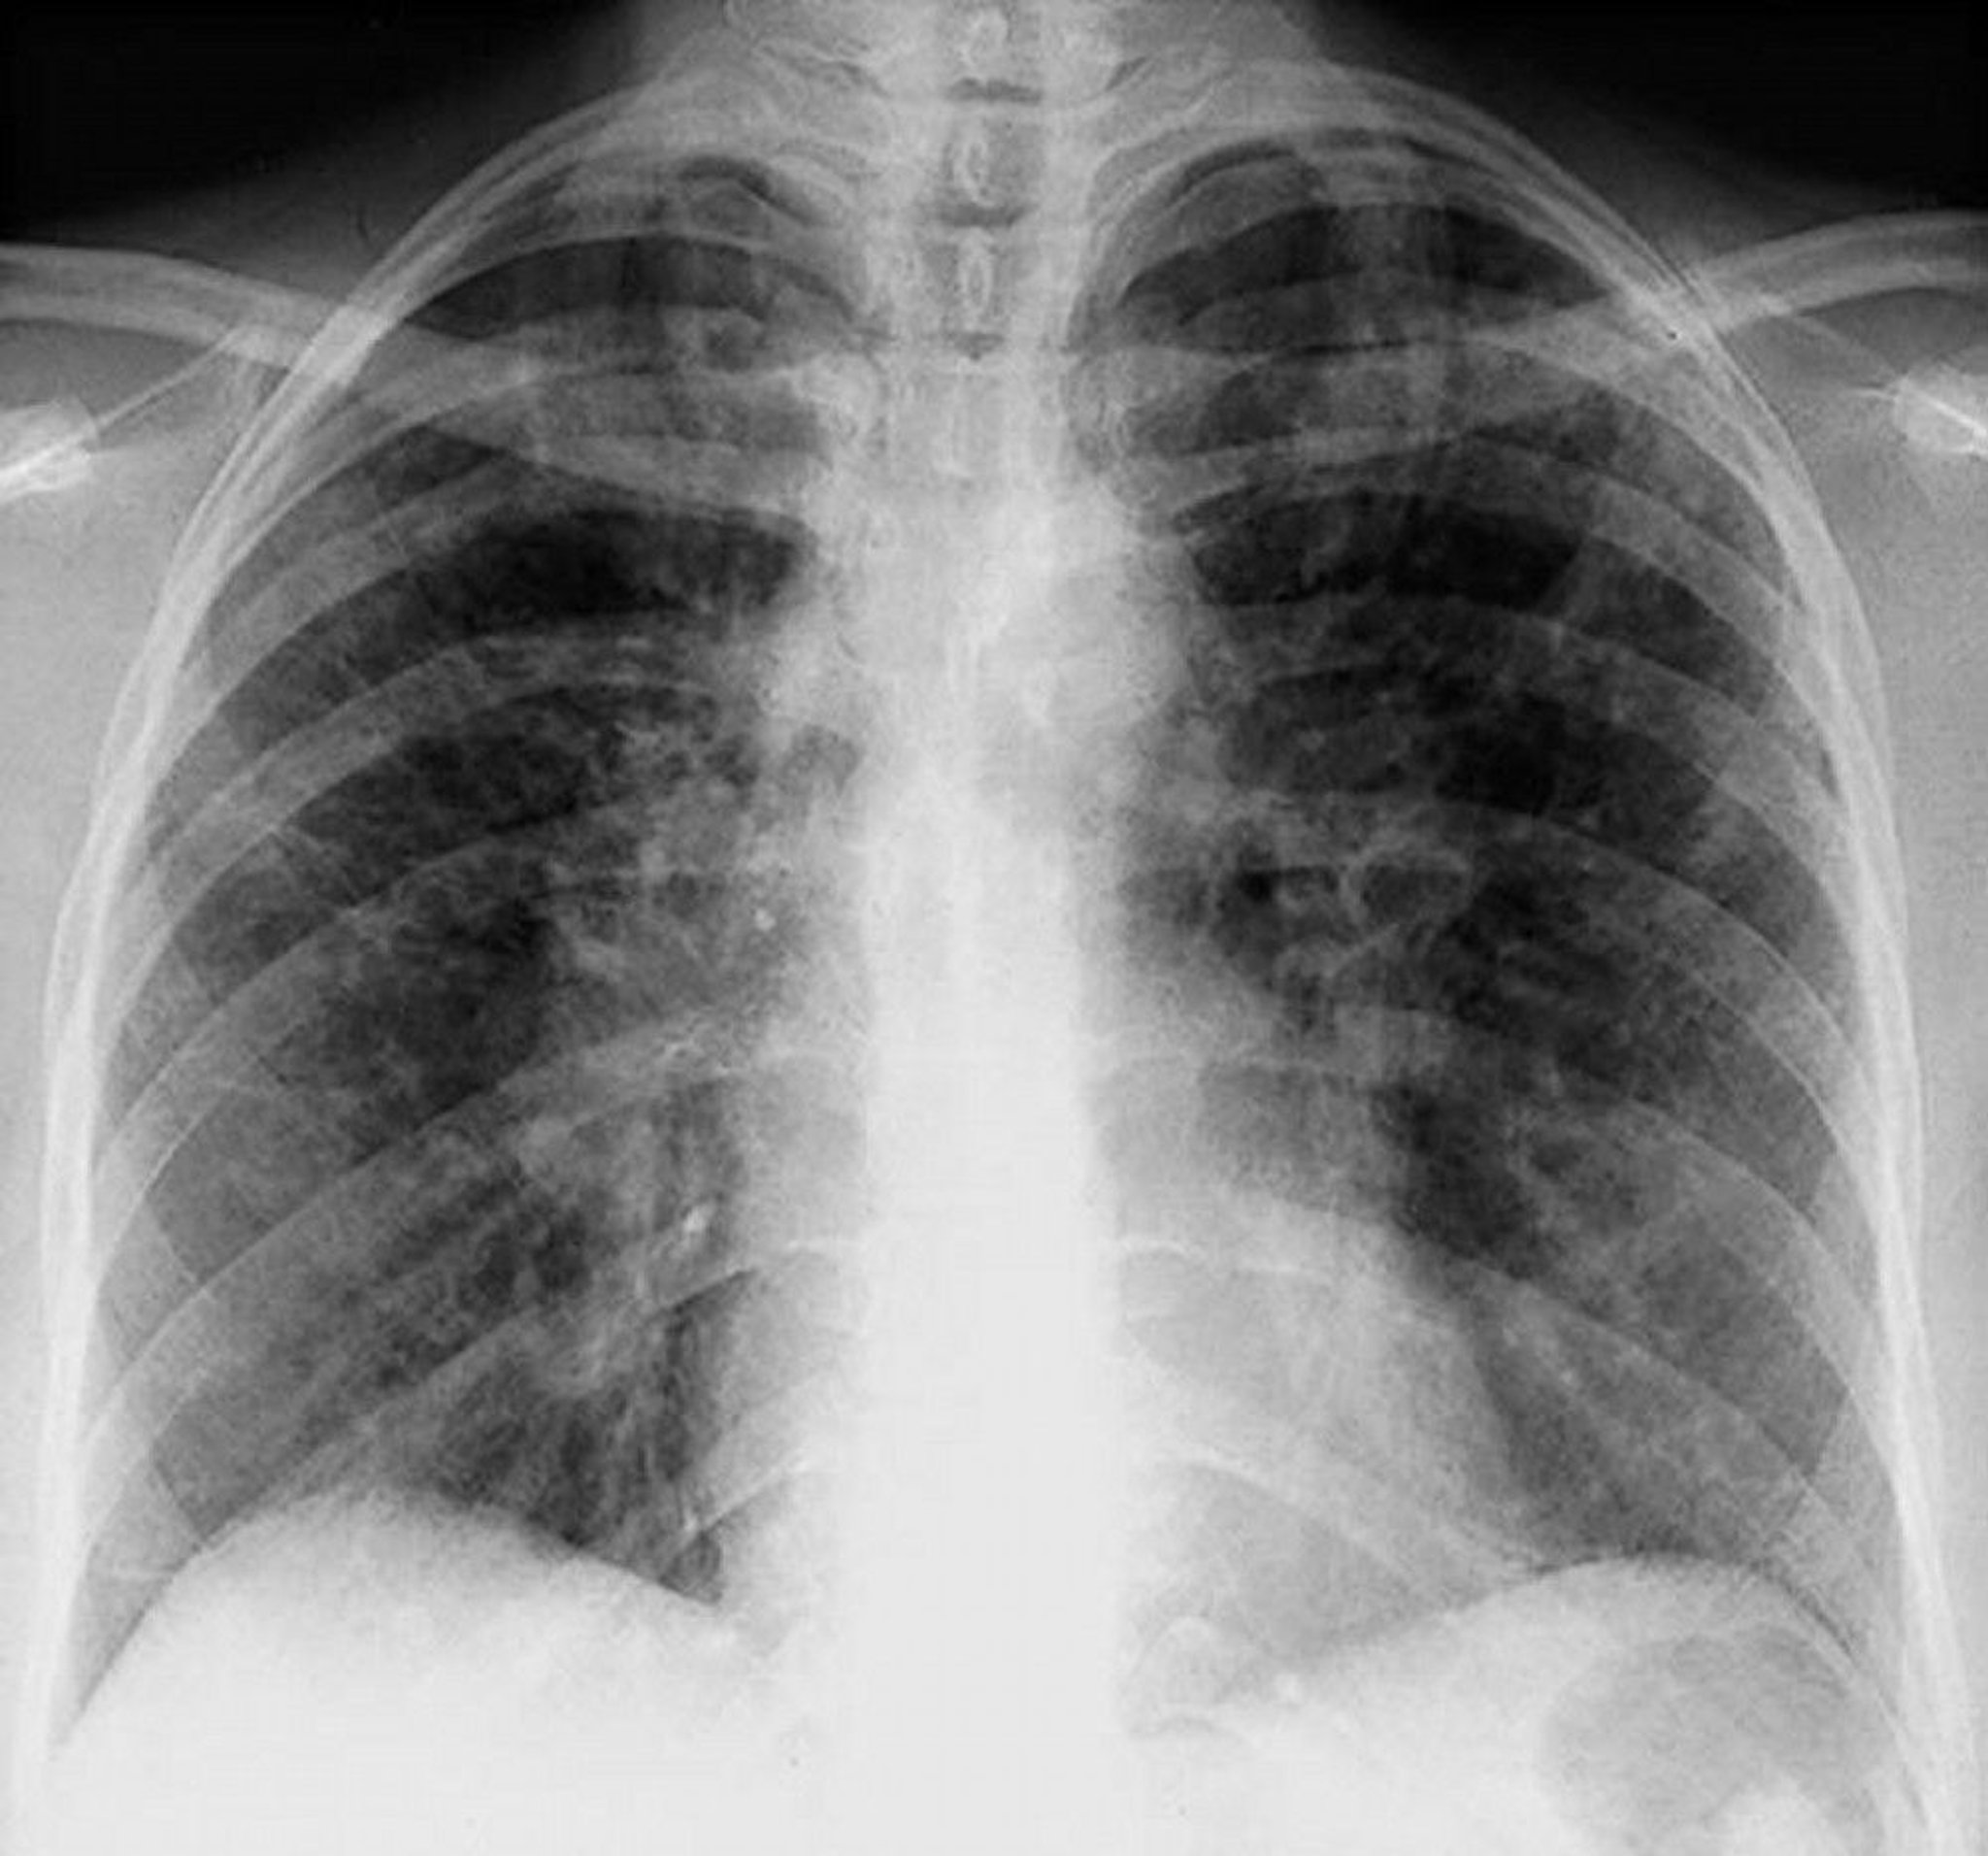

Sarcoidosis (Stage II)

Bilateral hilar adenopathy with interstitial opacities in stage II sarcoidosis.

By permission of the publisher. From Tanoue L, Elias J. In Bone's Atlas of Pulmonary and Critical Care Medicine. Edited by J Crapo. Philadelphia, Current Medicine, 2005.